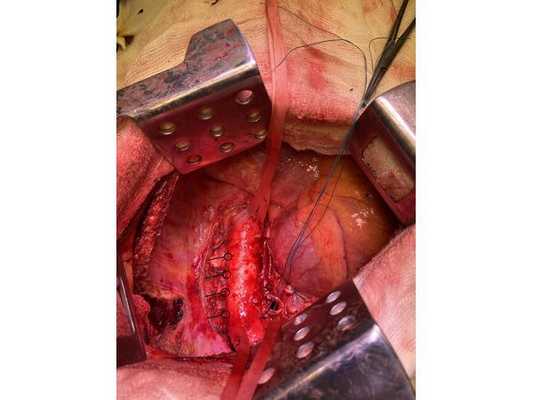

Интраоперационное фото: клипированные межрёберные артерии; аорта на тесёмочных держалках по краям зоны резекции адвентиции; культя главного бронха с провизорными швами при ушивании по Оверхольту

- боковая торакотомия (вскрытие грудной клетки) слева;

- пневмонэктомия с резекцией адвентиции (наружной оболочки) аорты, париетальной и медиастинальной плевры и мышечной стенки пищевода;

- медиастинальная лимфаденэктомия.

2. Выделены и взяты на держалки верхняя и нижняя лёгочные вены, выделен ствол лёгочной артерии, который также взят на держалку. Выполнено пробное пережатие лёгочной артерии — нарушений гемодинамики (движения крови по сосудам) и гемоксигенации (насыщения крови кислородом) нет.

3. Последовательно прошиты сшивающими аппаратами и пересечены нижняя и верхняя лёгочные вены и ствол лёгочной артерии. Выявлено, что опухоль подрастает к мышечной стенке пищевода, выполнена краевая резекция мышечной стенки пищевода на протяжении 2 см.

4. Острым путём отсечён левый главный бронх, при этом обнаружено, что опухоль распространяется перибронхиально. Культя левого главного бронха реампутирована (ампутирована повторно) в пределах визуально здоровой ткани стенки бронха, до 1,5-2 см от карины трахеи (гребня хряща между разделением двух главных бронхов). Центральная часть культи левого главного бронха ушита по Оверхольту.

5. Отступив по грудной стенке от края врастания опухоли в аорты на 2 см, рассечена и отсепарована (отделена хирургически) париетальная плевра и адвентиция аорты. Аорта мобилизована по типу "ручки чемодана" и взята на тесёмочные держалки выше и ниже места врастания опухоли.

6. Скелетизируя грудную стенку и аорту, с перевязкой левых межрёберных артерий, на участке рёбер 4, 5, 6 и 7 выполнена полуциркулярная резекция адвентиции аорты, мягких тканей грудной стенки с париетальной плеврой и тканей средостения.

7. Пневмонэктомия. Проверка аэростаза (герметичности) под уровнем жидкости — просачивания воздуха в области культи бронха нет.

8. Выполнена лимфодиссекция из области лёгочной связки, области бифуркации трахеи (места её разделения на главные бронхи), аортального окна, левого трахеобронхаильного угла и нижних паратрахеальных лимфатических узлов слева. Проверка гемостаза — сухо.

10. В плевральную полость заведён толстый силиконовый дренаж. Послойное ушивание раны, рёбра сведены тремя перикостальными швами. Наложена асептическая повязка.